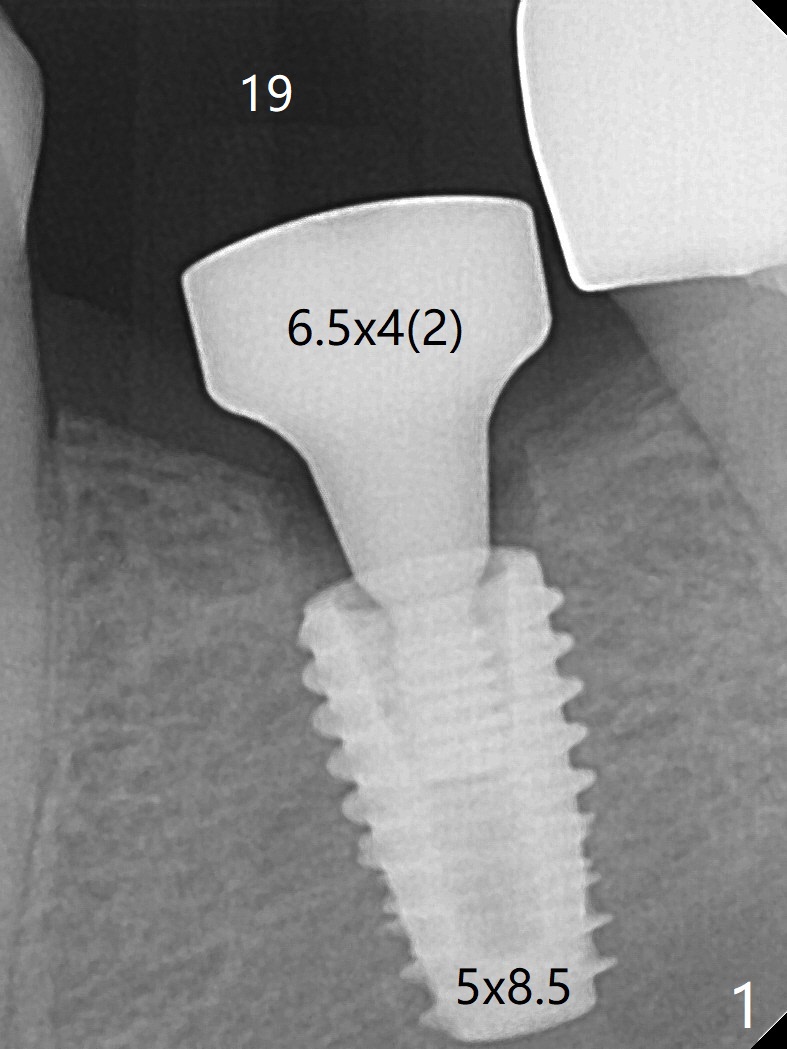

With one carpule of Xylocaine (34 mg with 17 mcg of Epinephrine), a 5x8.5 mm implant is placed at #19 in a timely and painless manner. The patient is pleased as compared to her previous implant placement at #3 and 30. Due to the thin buccal bone, the implant is placed ~.5 mm deeper than designed; a 6.5x4(2) mm healing abutment is incompletely seated (Fig.1). A smaller and skinny one (5.5x7(4) mm) is seated normally (Fig.2). Regional panoramic X-ray shows clearance from the Inferior Alveolar Canal (Fig.3 *). Although there is crestal bone resorption 6 months postop, the bone density next to the 1st thread is high (Fig.4 >). A 5.5x4(4) mm cemented abutment is placed for impression. The patient returns with #18 crown dislodgement and #19 crown loosening 11 months post cementation (Fig.5 <: gap between implant and abutment). Since the crown and abutment are unable to be torqued properly, they are removed (Fig.6). A narrower abutment is able to be seated apparently completely while a metal post (Fig.7 *) is tried in in the distal root of #18. To reduce the chance of re-fracture of #18 crown, the tooth #15 needs to be distalized orthodontically so that an implant will be placed at #14 (Fig.5).